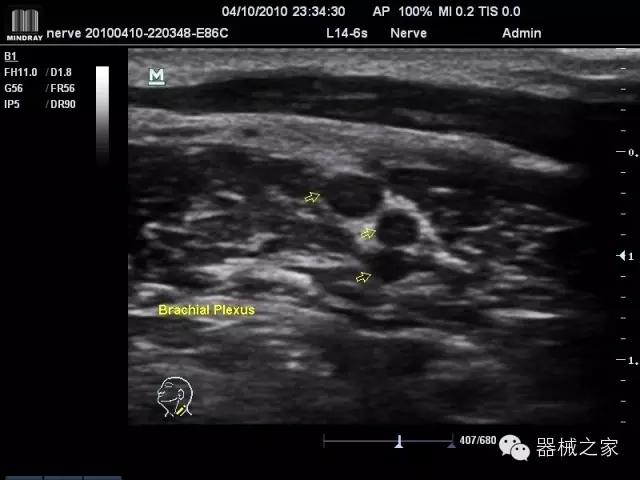

臨床圖片賞析

·優(yōu)秀的圖像效果、強(qiáng)大的功能體驗(yàn)、豐富的探頭選擇、合理的便攜式設(shè)計(jì),全中文顯示及病人管理界面,使得M7在任何場(chǎng)合、任何時(shí)候都能快速響應(yīng)更好的心血管、腹部、婦產(chǎn)、小器官等常規(guī)超聲檢查以及肌骨、神經(jīng)、顱腦、術(shù)中等新興領(lǐng)域的使用需求;